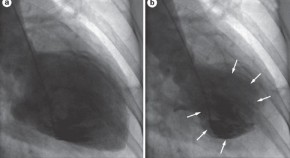

• Ramcharitar and colleagues present an interesting case of a patient with drug-refractory hypertrophic obstructive cardiomyopathy and NYHA class II–III heart failure who was treated with septal coil embolization. This article demonstrates, for the first time, the acute changes in hemodynamics that occur following septal coil embolization, and shows that this treatment is a viable alternative to percutaneous coronary intervention.